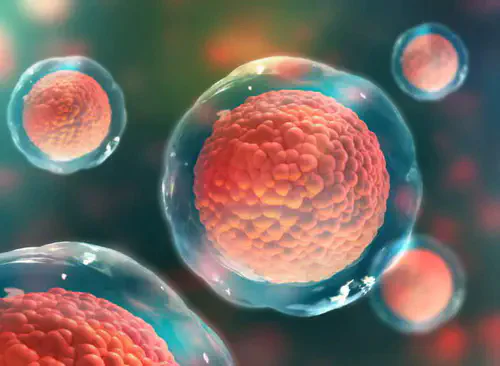

Estágio 1: Acúmulo de gordura nas células do fígado

A dieta moderna faz uso intensivo de açúcares e carboidratos, que são convertidos em gordura pelo corpo. Isso pode resultar no acúmulo de gordura nas células do fígado.

Estágio 2: Resposta Inflamatória

Esse acúmulo de gordura nas células do fígado causa uma resposta inflamatória auto-imune, na qual anticorpos são enviados para atacar o próprio órgão.

A Causa Biológica de um Fígado Gordo

Os pesquisadores identificaram a "mãe de todos os antioxidantes", que protege o fígado contra a inflamação.